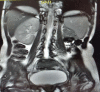

Mayer-Rokitansky-Kuster-Hauser (MRKH) syndrome and 18p deletion syndrome, two genetic disorders having distinct genetic etiologies, have an exceedingly rare likelihood of coexistence. Vaginal agenesis or MRKH syndrome, the developmental failure of Mullerian ductal system-derived structures in a genotypic female fetus (46, XX), leads to congenital absence of uterus and vagina in variable degree. The 18p deletion syndrome is a rare chromosomal disorder, characterized by dysmorphic features, stunted growth, and mental retardation, which is caused by deletion of a part or all of the short arm of chromosome 18. A detailed evaluation of primary amenorrhea in a 16-year-old girl yielded both MRKH syndrome and 18p deletion syndrome. Extensive literature search could not identify any reported case bearing this combination of syndromes. This case presentation and review emphasizes on the importance of karyotyping in MRKH patients having atypical features.